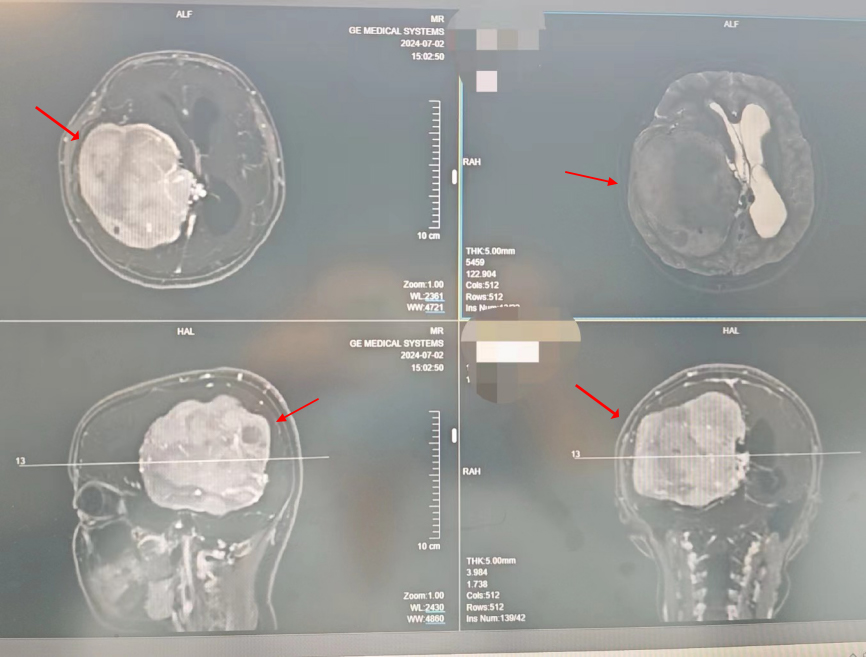

查看详情15岁少女脑袋里长了一个拳头大小的肿瘤,犹如一颗“炸弹”,如不及时进行手术,将面临瘫痪甚至是死亡的危险。近日,真人电子网址神经外科刘文科副教授团队成功为一位15岁的患者实施...